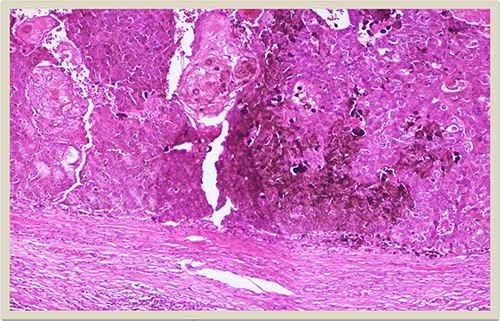

A 69-year-old man was admitted to our hospital with a nodular skin tumor of the back (Fig. 1). The patient had no ongologic history. We performed excisional biopsy that revealed collision tumor. The collision tumor consisted of mixed melanosquamous tumor (dermal squamomelanocytic tumor) together with BCC (Fig. 2). The BCC was superficial spreading. The mixed element contained squamous cell carcinoma of well/moderately differentiated and a neoplasm with melanotic characteristics, which due to cell atypia, presence of mitoses and high index of cell proliferation (Ki67: 80%) was described as melanoma (Fig. 3). Diagnosis of the melanotic and the squamous element was confirmed with immunohistochemistry (Figs 4 and 5).

p63 × 10: p63 immunostain confirms the presence of squamous cell carcinoma component (×10 magnification).

Histologically the collision tumor involves two different and distinct entities. There is no interaction between the tumor cells of the two different neoplasms. The paradox in our case is that the melanotic cells were admixed with squamous cells. The histopathologic findings of the combined tumor were confirmed with immunohistochemistry. Squamous element was confirmed from the positivity of the stains: AE1/AE3, EMA and CK5. Melanotic element was also confirmed with the following stains: Vimentin, S-100, MART-1(Melan-A) and HMB45. Histologic findings and immunohistochemical stains confirmed the combined melanosquamous neoplasm in the collision tumor, which does not seem to involve epidermis. Reviewing the literature, we did not find any other case of a combined neoplasm in a collision formation.